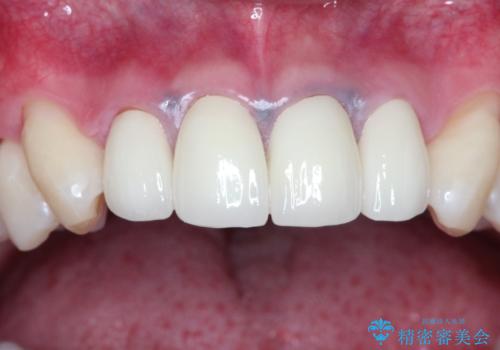

前歯とメタルタトゥー見た目が気になる 矯正・セラミックを組み合わせた治療

- 上の前歯の見た目が気になるとのことで来院されました。

上の前歯の4本が神経の処置がされており、前から2番目の歯が内側に入り込んでしまっていました。

また、金属で治療された根本の歯茎が黒く変色(メタルタトゥー)しており、余計に見た目がよくない状態となっておりました。

矯正治療で前歯の歯並びを整えてからセラミックほ装着する計画としました。